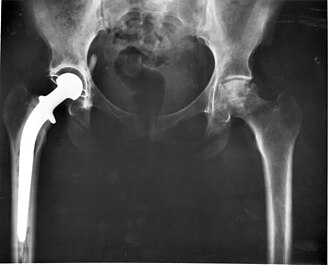

- Zamjena zgloba je kirurška metoda uklanjanja oboljelih ili oštećenih kostiju i drugih struktura zgloba i njihova zamjena ručno ili strojno izrađenim protezama od metala i/ili plastike). Najčešće se primjenjuje kod zamjene zgloba koljena i kuka. U zadnje vrijeme, zahvaljujući suvremenim materijalima može se obavljati zamjena nekih drugih zglobova, kao npr. oboljelih kralježaka.

Prognoza kod bolesnika s artrozom kod kojih je uspješno izvedena kirurška zamjena zgloba kuka i koljena protezom (artroplastika), je povoljna u više od 90% slučajeva [1] Ugrađena se proteza ipak mora zamijeniti 10 do 15 godina nakon ugradnje, ovisno o starosti pacijenta i bavljenju fizičkom aktivnosti. Kod mlađih i aktivnijih pacijenata češća je potreba za zamjenom proteze, dok kod većine starijih pacijenata zamjena nije potrebna.